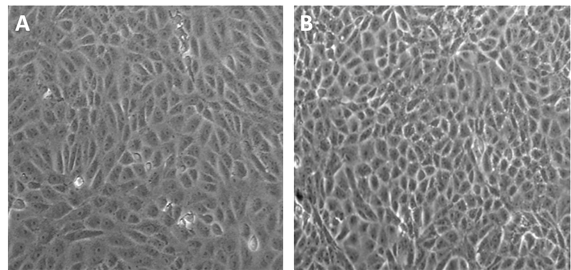

使用Sheff-Vax添加物可以實現(xiàn)Vero細(xì)胞的無血清培養(yǎng),逐步減少血清用量直至完全去除血清后,Vero細(xì)胞生長形態(tài)無顯著變化(見下圖)

Vero細(xì)胞生長形態(tài)對比

A)對照組:DMEM+10%胎牛血清;

B)實驗組:DMEM+0%胎牛血清+2g/L Sheff-Vax ACF+10mg/L rInsulin

每次傳代逐步減少FBS,同時添加Sheff-Vax ACF,在相同培養(yǎng)時間內(nèi),無血清組細(xì)胞生長密度可達(dá)到10% FBS組細(xì)胞密度峰值的一半,延長培養(yǎng)時間還可以獲得更高的細(xì)胞密度(見下圖)。